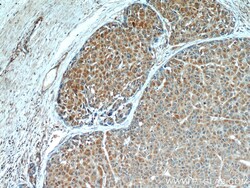

- Immunohistochemistry of paraffin-embedded mouse testis tissue slide using 14412-1-AP (PEG10 Antibody) at dilution of 1:25 (under 10x lens).

- Submitted by

- Invitrogen Antibodies (provider)

- Main image

- Experimental details

- Immunohistochemistry of paraffin-embedded mouse testis tissue slide using 14412-1-AP (PEG10 Antibody) at dilution of 1:25 (under 40x lens).